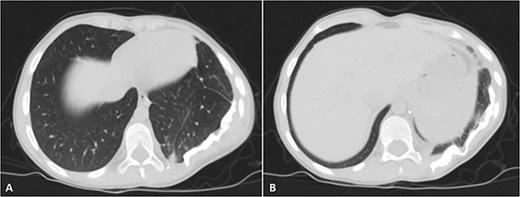

His postoperative course was uneventful. A chest CT was performed following the surgery, and the results revealed that the previous left lung mass had been completely removed without definite residue (Fig. 4). The patient is on close follow-up monthly with a physical exam, chest X-ray, and chest CT every 3–6 months. For the past two years, there have been no discernible clinical or radiological indicators of recurrence (Fig. 5).

Selected axial cuts of the patient’s chest–lung window. The previously mentioned left posterior chest wall mass is no longer seen with post-operative changes noted.